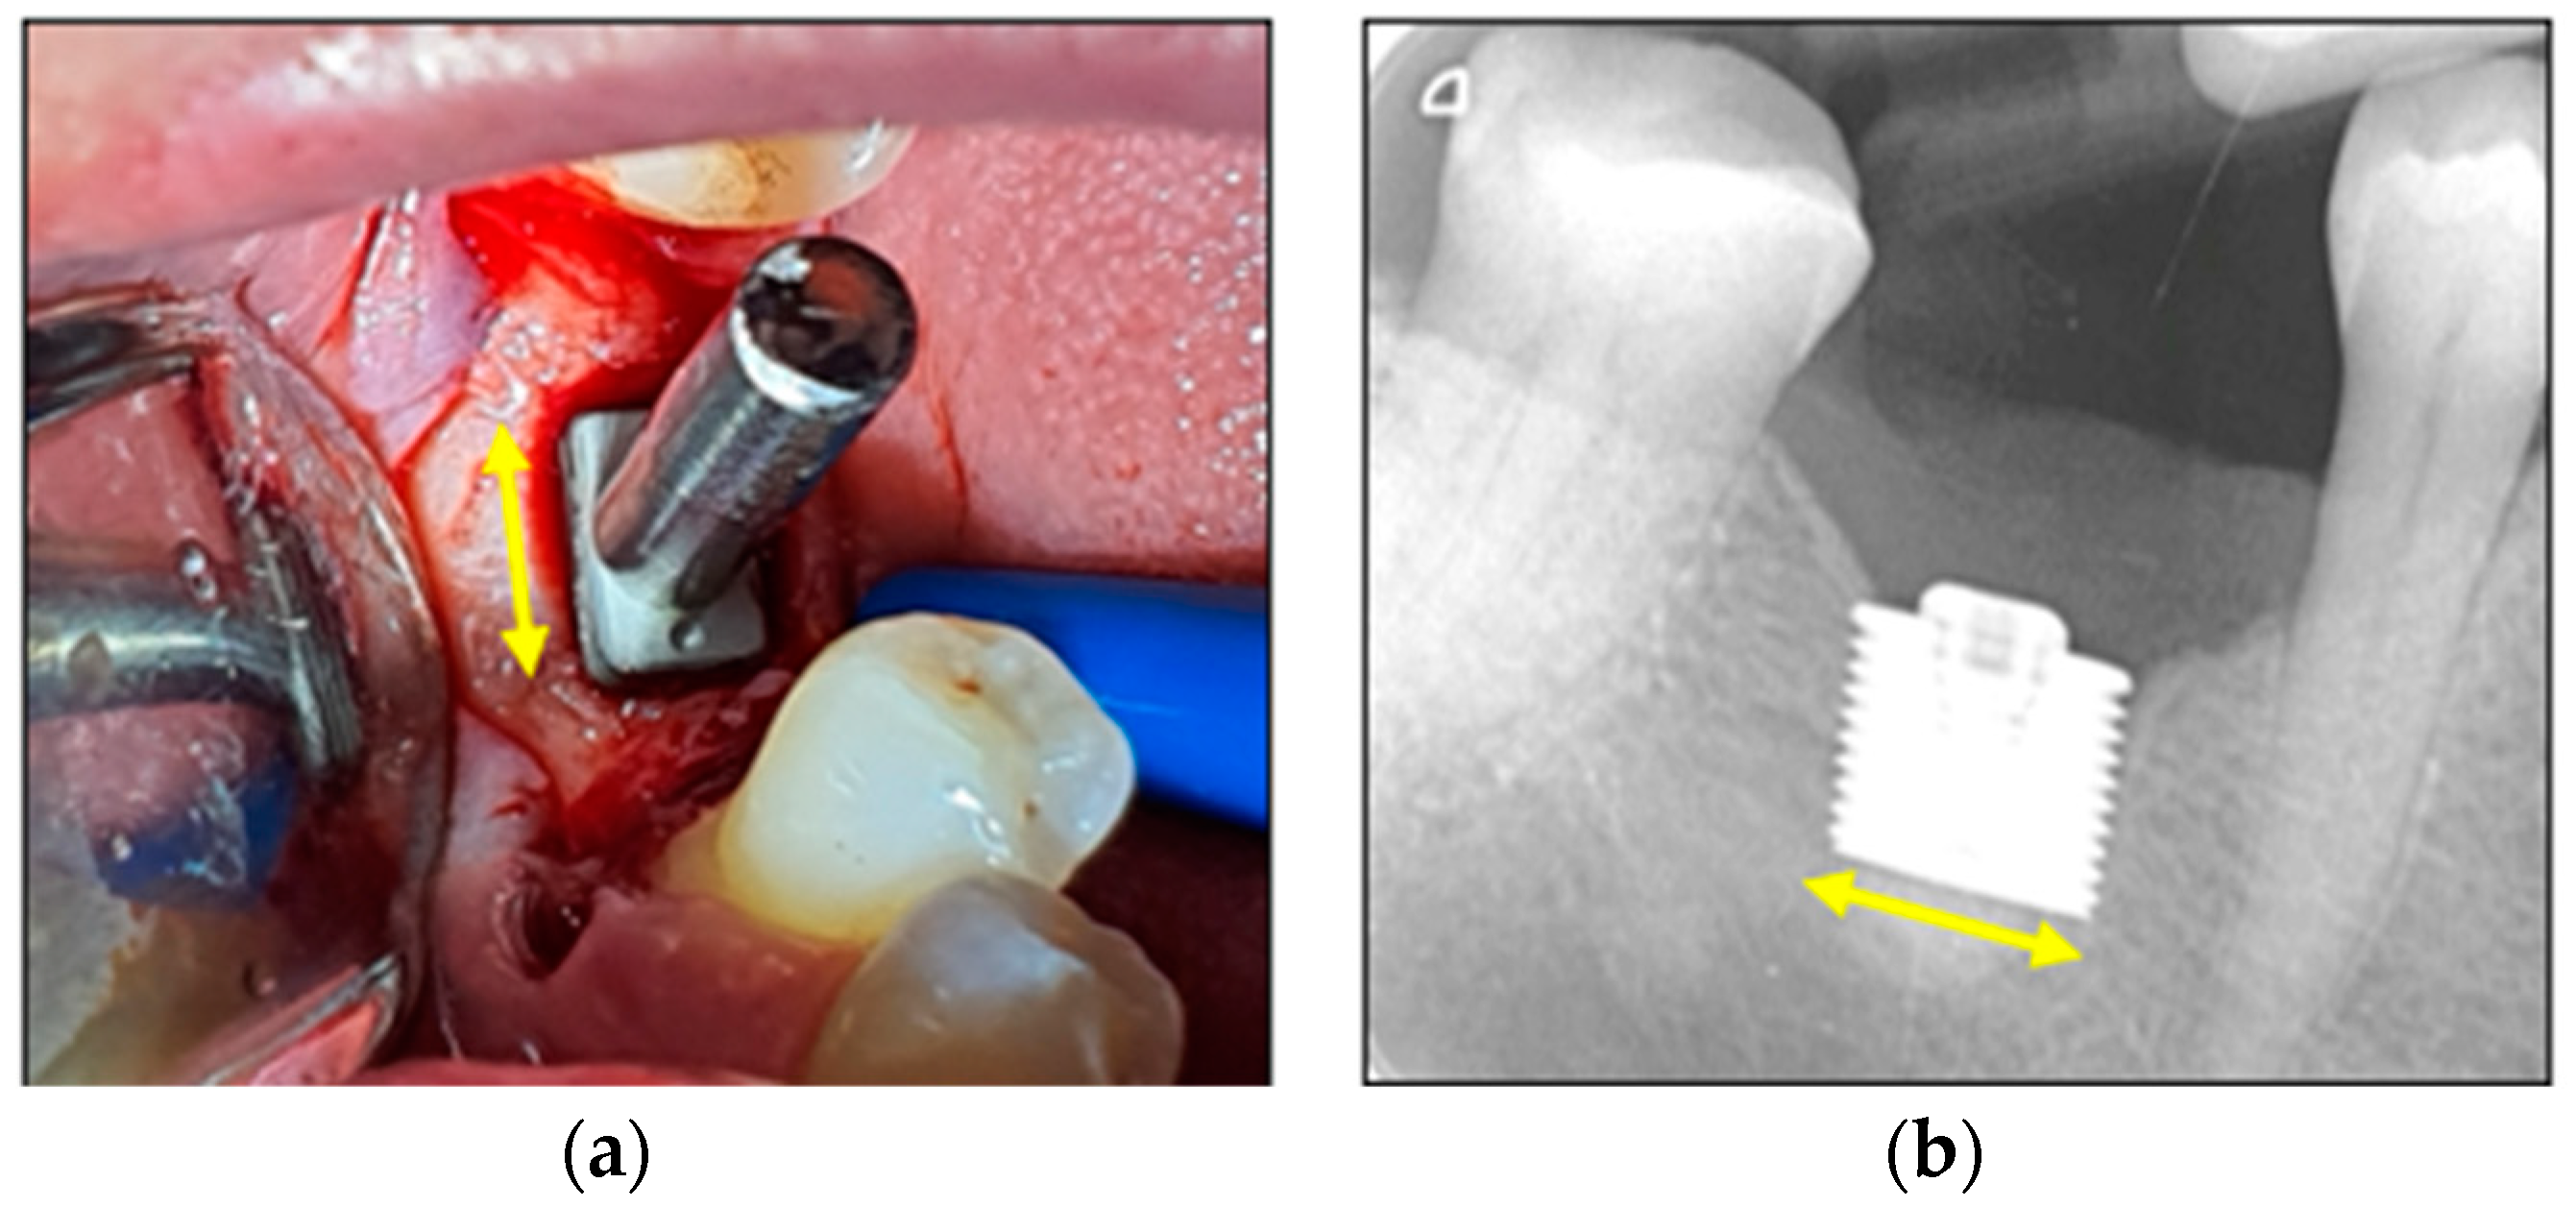

3.3.1. Clinical Images